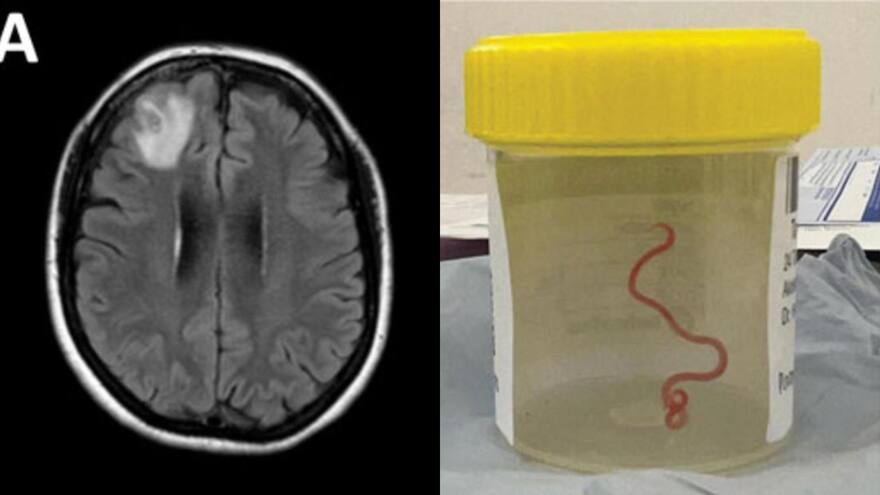

hospital de Camberra